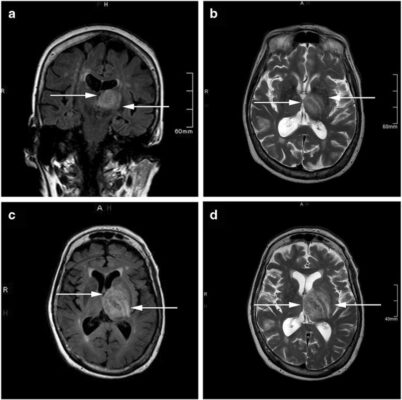

3. تصویربرداری مغز: ممکن است از روشهای تصویربرداری مغزی مانند اسکن MRI (تصویربرداری مغناطیسی هستهای) استفاده شود تا تغییرات و التهاب مغز را نشان دهد که ممکن است به علائم بیماری آمیب مغزخوار اشاره کند.